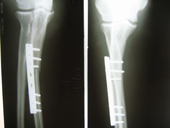

| Fracture Femur |

Interlocking nailing femur |